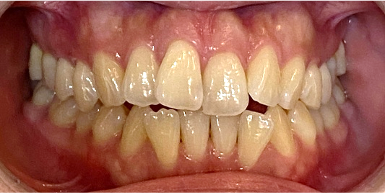

34歳女性のビフォーアフター

| 診断 | 叢生(デコボコがある状態)、開咬、下顎前突 |

| 治療方針 | インビザラインシステムにて主にIPR(歯と歯の間をわずかに削合してスペースを獲得する方法)を組み込んだ動的矯正治療を行った叢生改善と、開咬の改善のため臼歯部圧下をメインとした動的治療を行い、保定を行う。 |

| 治療費 ※ | 99万7千円(診断、型取り、PMTC、保定装置を含む料金) |

| 治療期間 | 3年5か月 |

| リスク | 1日20時間以上マウスピースを使用できない場合、歯が動かない可能性がある。装着時や食事時に痛みを伴う。歯肉退縮や虫歯になるおそれがある。また、指導通りに装着できていない場合や適切なブラッシングが出来ていないとそのリスクが高くなる。歯根が短くなることがある。ごくまれに歯の神経が損傷してしまうことがある。過去にぶつけたり深い虫歯治療をしたことがあるとそのリスクはやや高くなる。矯正後には保定装置が必要。適切な使用ができない場合、後戻りの原因となる。将来的に歯並びが動いて再矯正が必要な場合がある。舌癖が強い場合や正常に生えていない親知らずがある場合、その可能性が高くなる。 |